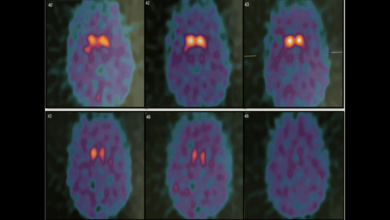

Complicación infecciosa tras estimulación cerebral profunda en tratamiento en joven con Parkinson juvenil

El paciente usó marihuana como forma de control sintomático en lugar de seguir el tratamiento psicológico recomendado. Gammagrafía del transportador…